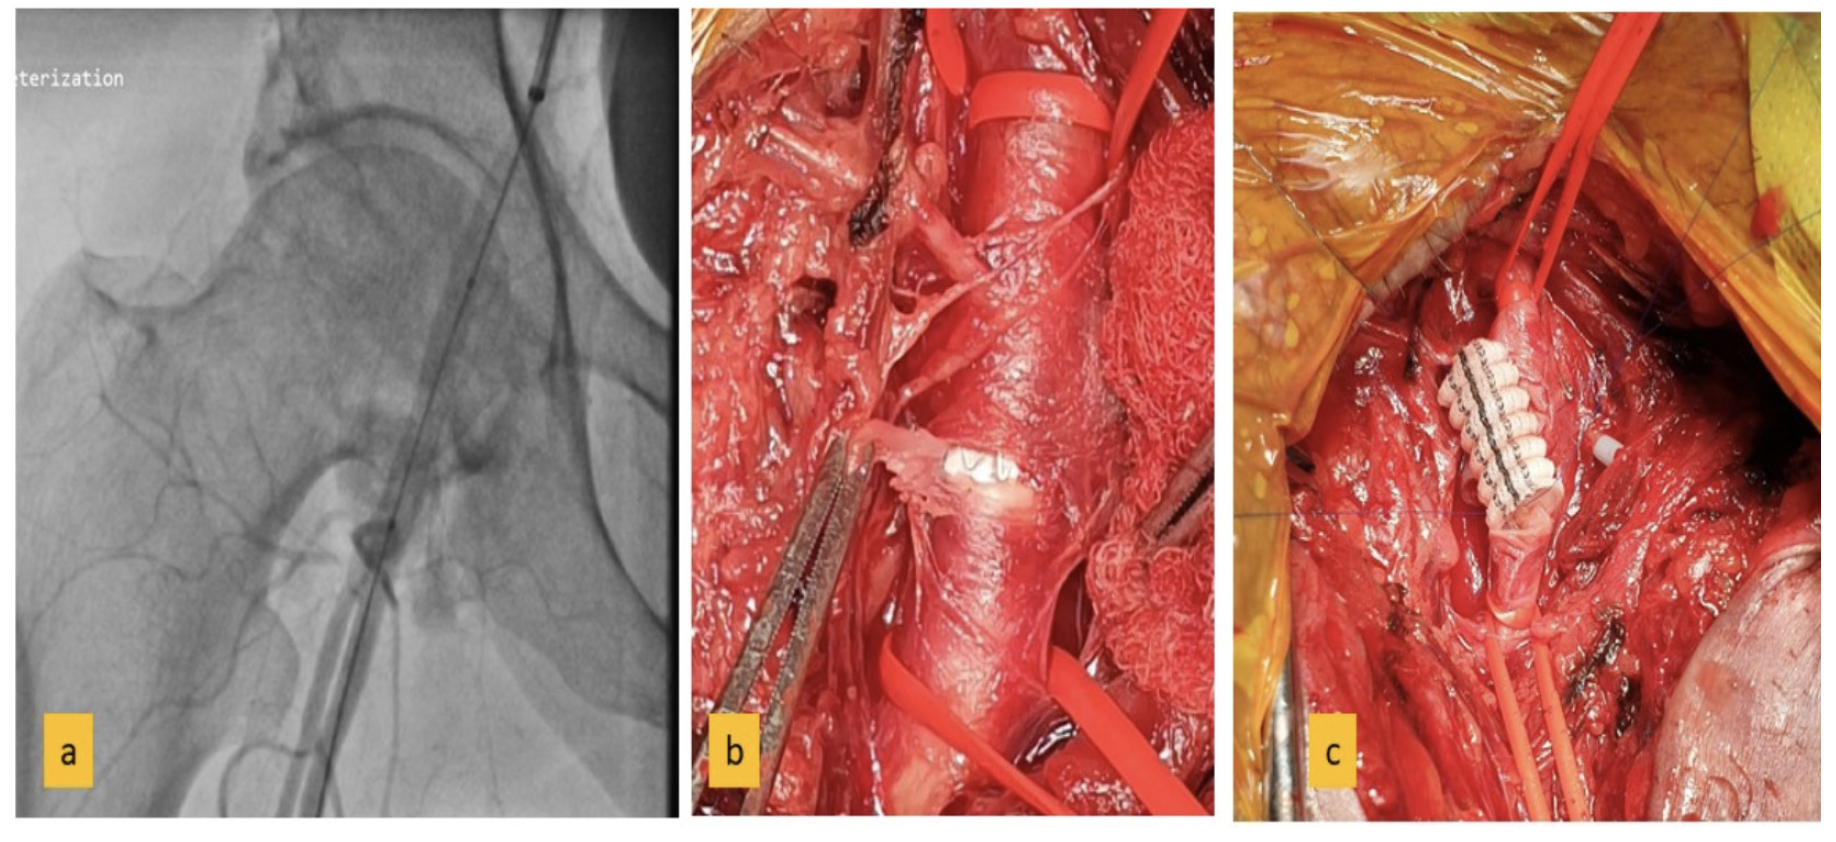

This was followed by a sudden spurt of blood. Manual compression didn’t stop the bleeding. Left femoral access was taken and an angiogram was done using Judkins right (6 Fr) catheter placed in right external iliac artery. Angiogram revealed a large rent in the common femoral artery with spurting of blood (Figure 1a, Supplemental Video) as the manual compression was released momentarily.

A 7 x 37 mm covered stent was unsuccessfully deployed in the right common femoral artery (Figure 2a), and the patient was taken up for open vascular closure. Preop revealed a 5 mm rent in the common femoral artery, which was successfully closed using a 7 mm Dacron interposition graft achieving complete hemostasis (Figures 2b and 3c).